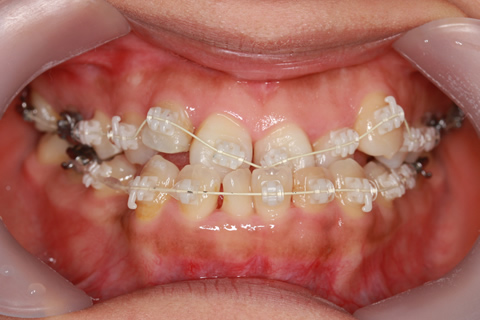

受け口(反対咬合)の症例

症例一覧